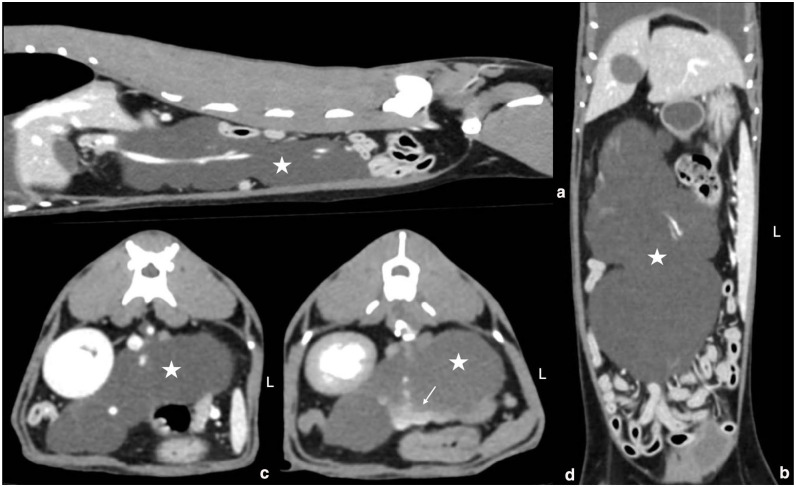

Case summary: An 8-year-old female spayed Russian Blue cat presented for acute progressive dyspnoea. The patient had pleural effusion and was diagnosed with chylothorax. A multiphase contrast-enhanced CT scan of thoracic and abdominal cavities was performed to facilitate diagnosis and surgical planning. Incidentally, a large lobulated, elongated, cystic and encapsulated peritoneal mass was found. Contrast pooled within the peritoneal mass during lymphography, suggesting lymphatic origin. The patient was eventually euthanased as a result of recurrence of chylothorax. Necropsy revealed multiple irregular, thin-walled pockets of chylous fluid pooling within the mesentery. Histopathology of the affected mesentery was compatible with a diagnosis of lymphatic malformation.

Relevance and novel information: To the authors' knowledge, this is the first case describing a feline presentation of mesenteric lymphatic malformation. This is also the first case reporting the presentation of chylothorax for a veterinary patient with mesenteric lymphatic malformation.